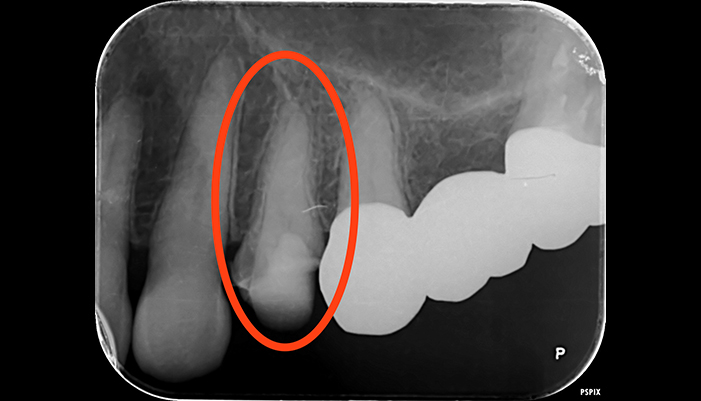

治療前

治療後

| 主訴 | 歯茎が腫れている |

|---|---|

| 治療期間 | 2回 |

| 費用 | 再根管治療154,000円(税込)+ ファイバーコア44,000円(税込)= 198,000円(税込) |

| 治療内容 | ラバーダムを用いて無菌的な環境下で根管治療を行いました。 マイクロスコープ下で虫歯を完全に取り切り、NiTiファイルを用いた根管形成、薬液や超音波器具による洗浄、その後根管内をさらに消毒するため水酸化カルシウムを入れて仮の蓋をしました。 2回目は体に馴染みの良い材質による充填、被せ物を支え、再感染しないように土台を立てました。 |